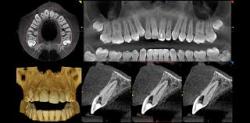

Dental cone beam computed tomography (CT) is a special type of x-ray machine used in situations where regular dental or facial x-rays are not sufficient. It is not used routinely because the radiation exposure from this scanner is significantly more than regular dental x-rays. See the Safety page for more information about x-rays. This type of CT scanner uses a special type of technology to generate three dimensional (3-D) images of dental structures, soft tissues, nerve paths and bone in the craniofacial region in a single scan. Images obtained with cone beam CT allow for more precise treatment planning.

With cone beam CT, an x-ray beam in the shape of a cone is moved around the patient to produce a large number of images, also called views. CT scans and cone beam CT both produce high-quality images.

Cone beam CT provides detailed images of the bone and is performed to evaluate diseases of the jaw, dentition, bony structures of the face, nasal cavity and sinuses. It does not provide the full diagnostic information available with conventional CT, particularly in evaluation of soft tissue structures such as muscles, lymph nodes, glands and nerves. However, cone beam CT has the advantage of lower radiation exposure compared to conventional CT.

During a cone beam CT examination, the C-arm or gantry rotates around the head in a complete 360-degree rotation while capturing multiple images from different angles that are reconstructed to create a single 3-D image.

The x-ray source and detector are mounted on opposite sides of the revolving C-arm or gantry and rotate in unison. In a single rotation, the detector can generate anywhere between 150 to 200 high resolution two-dimensional (2-D) images, which are then digitally combined to form a 3-D image that can provide your dentist or oral surgeon with valuable information about your oral and craniofacial health.

- Cone beam CT scans provide more information that conventional dental x-ray, allowing for more precise treatment planning.